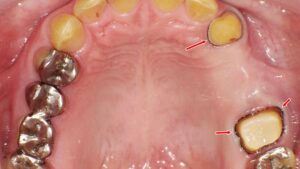

前歯4本の歯槽膿漏、抜歯すべき?それとも治療で残せる?

前歯4本の歯槽膿漏が進行し、抜歯やインプラントを提案された方へ。江戸川区篠崎の当院では、CT診断や再生治療の可否を含め、歯を残す可能性も慎重に検討します。矯正中でも対応可能で、骨の状態に応じた最適な治療をご提案。不安な方はセカンドオピニオンも歓迎します。丁寧な説明と納得の診療で、安心してご相談いただけます。